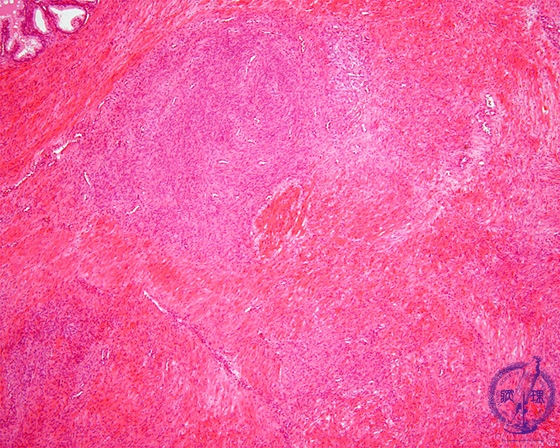

Histology (HE stain, low power): Nodular hyperplasia of interstitial fibromuscular tissue (stromal hyperplasia, yellow dotted line).Compare stromal hyperplasia with glandular hyperplasia.。